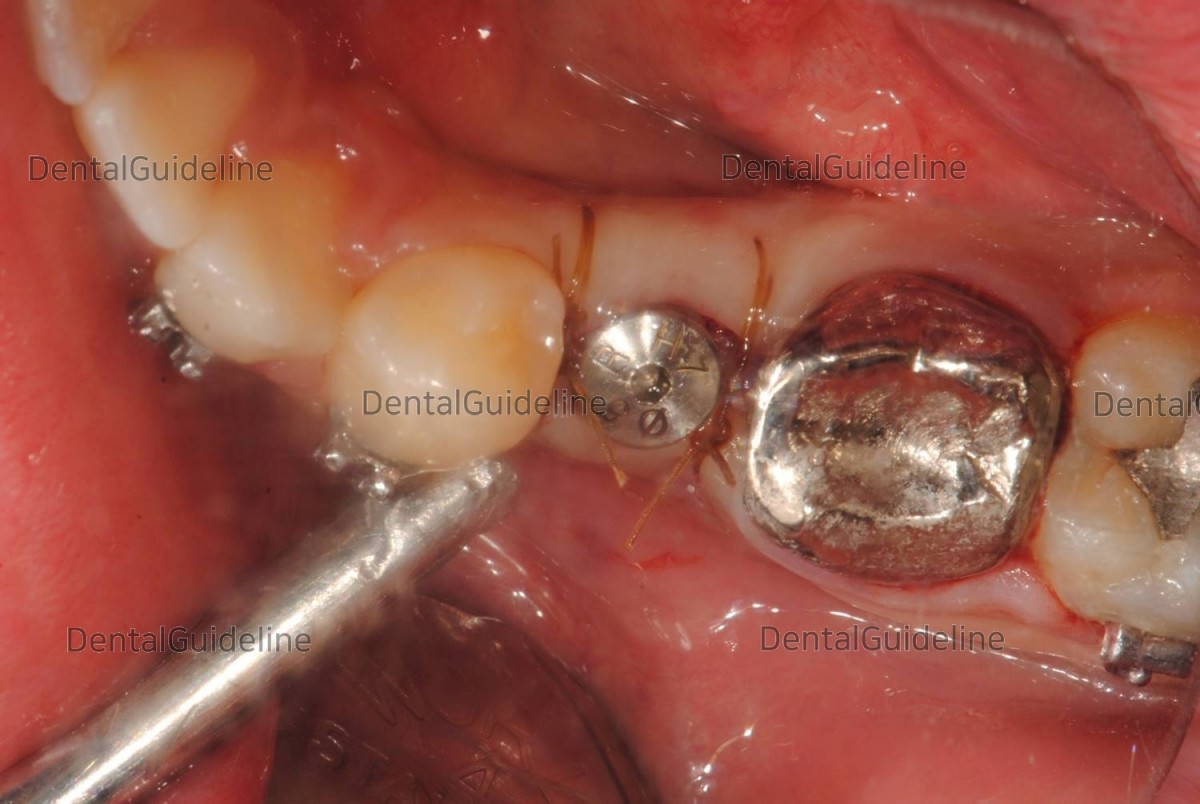

Healing abutment engagement and suture